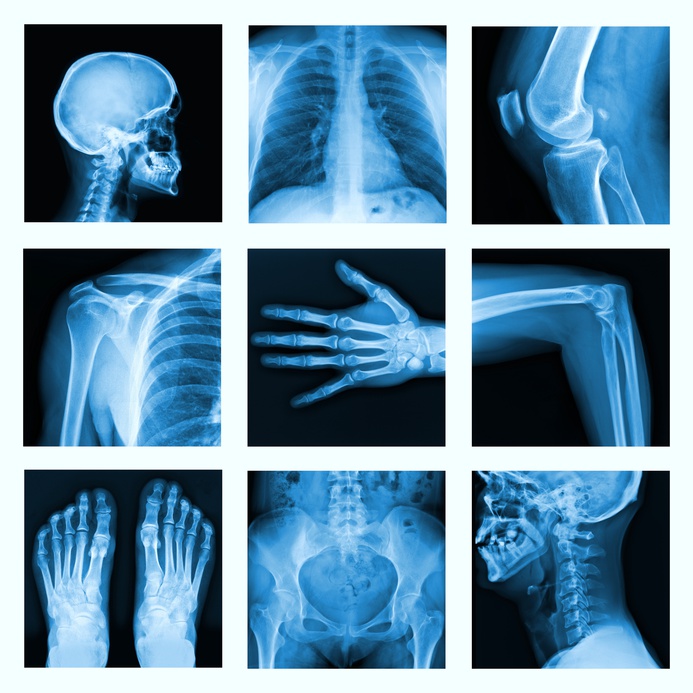

Teleradiología

La teleradiología es la tecnología para la transmisión de imágenes radiológicas de pacientes para el acceso a estudios realizados para realizar actividad diagnóstica o para compartir dichos estudios entre diferentes especialistas para su interpretación o consulta.